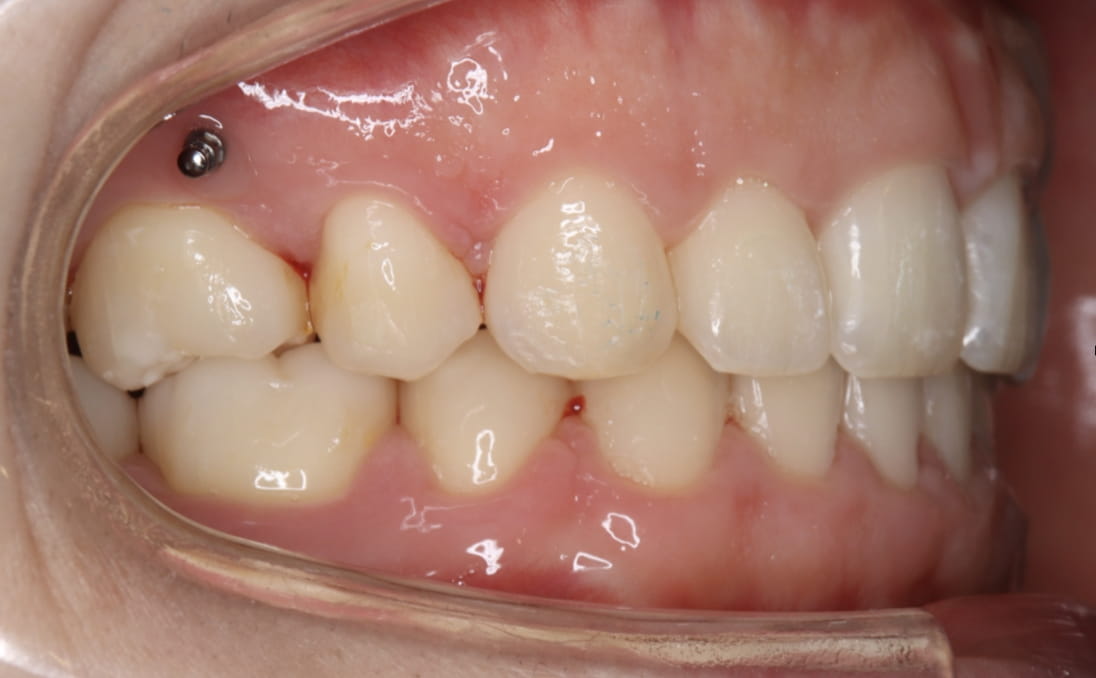

《上下顎前突》

症例

主訴 口ゴボが気になる

治療装置 表側ワイヤー矯正・アンカースクリュー

抜歯 抜歯あり

診断名 上下顎前突(口ゴボ)

副作用 歯肉退縮・歯根吸収・歯髄・壊死・癒着による予期せぬ歯の動き

アンカースクリューで前歯を最大限に後退。Eラインの内側に唇が収まり、顎の梅干しシワも解消。横顔のシルエットが劇的に改善した症例。

他院で抜歯なし矯正を行ったが口ゴボが残存。来院時は上顎に固定式ワイヤーが入った状態。CT分析→抜歯+アンカー埋入で劇的に改善。22歳・奈良市。

治療前

治療中①

治療中②

治療中③

治療後